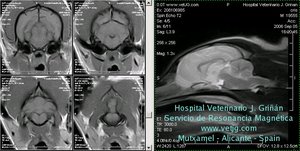

Detalle del metencéfalo canino mediante MRI. Cortes transversales pot. en T1 y corte sagital pot en T2